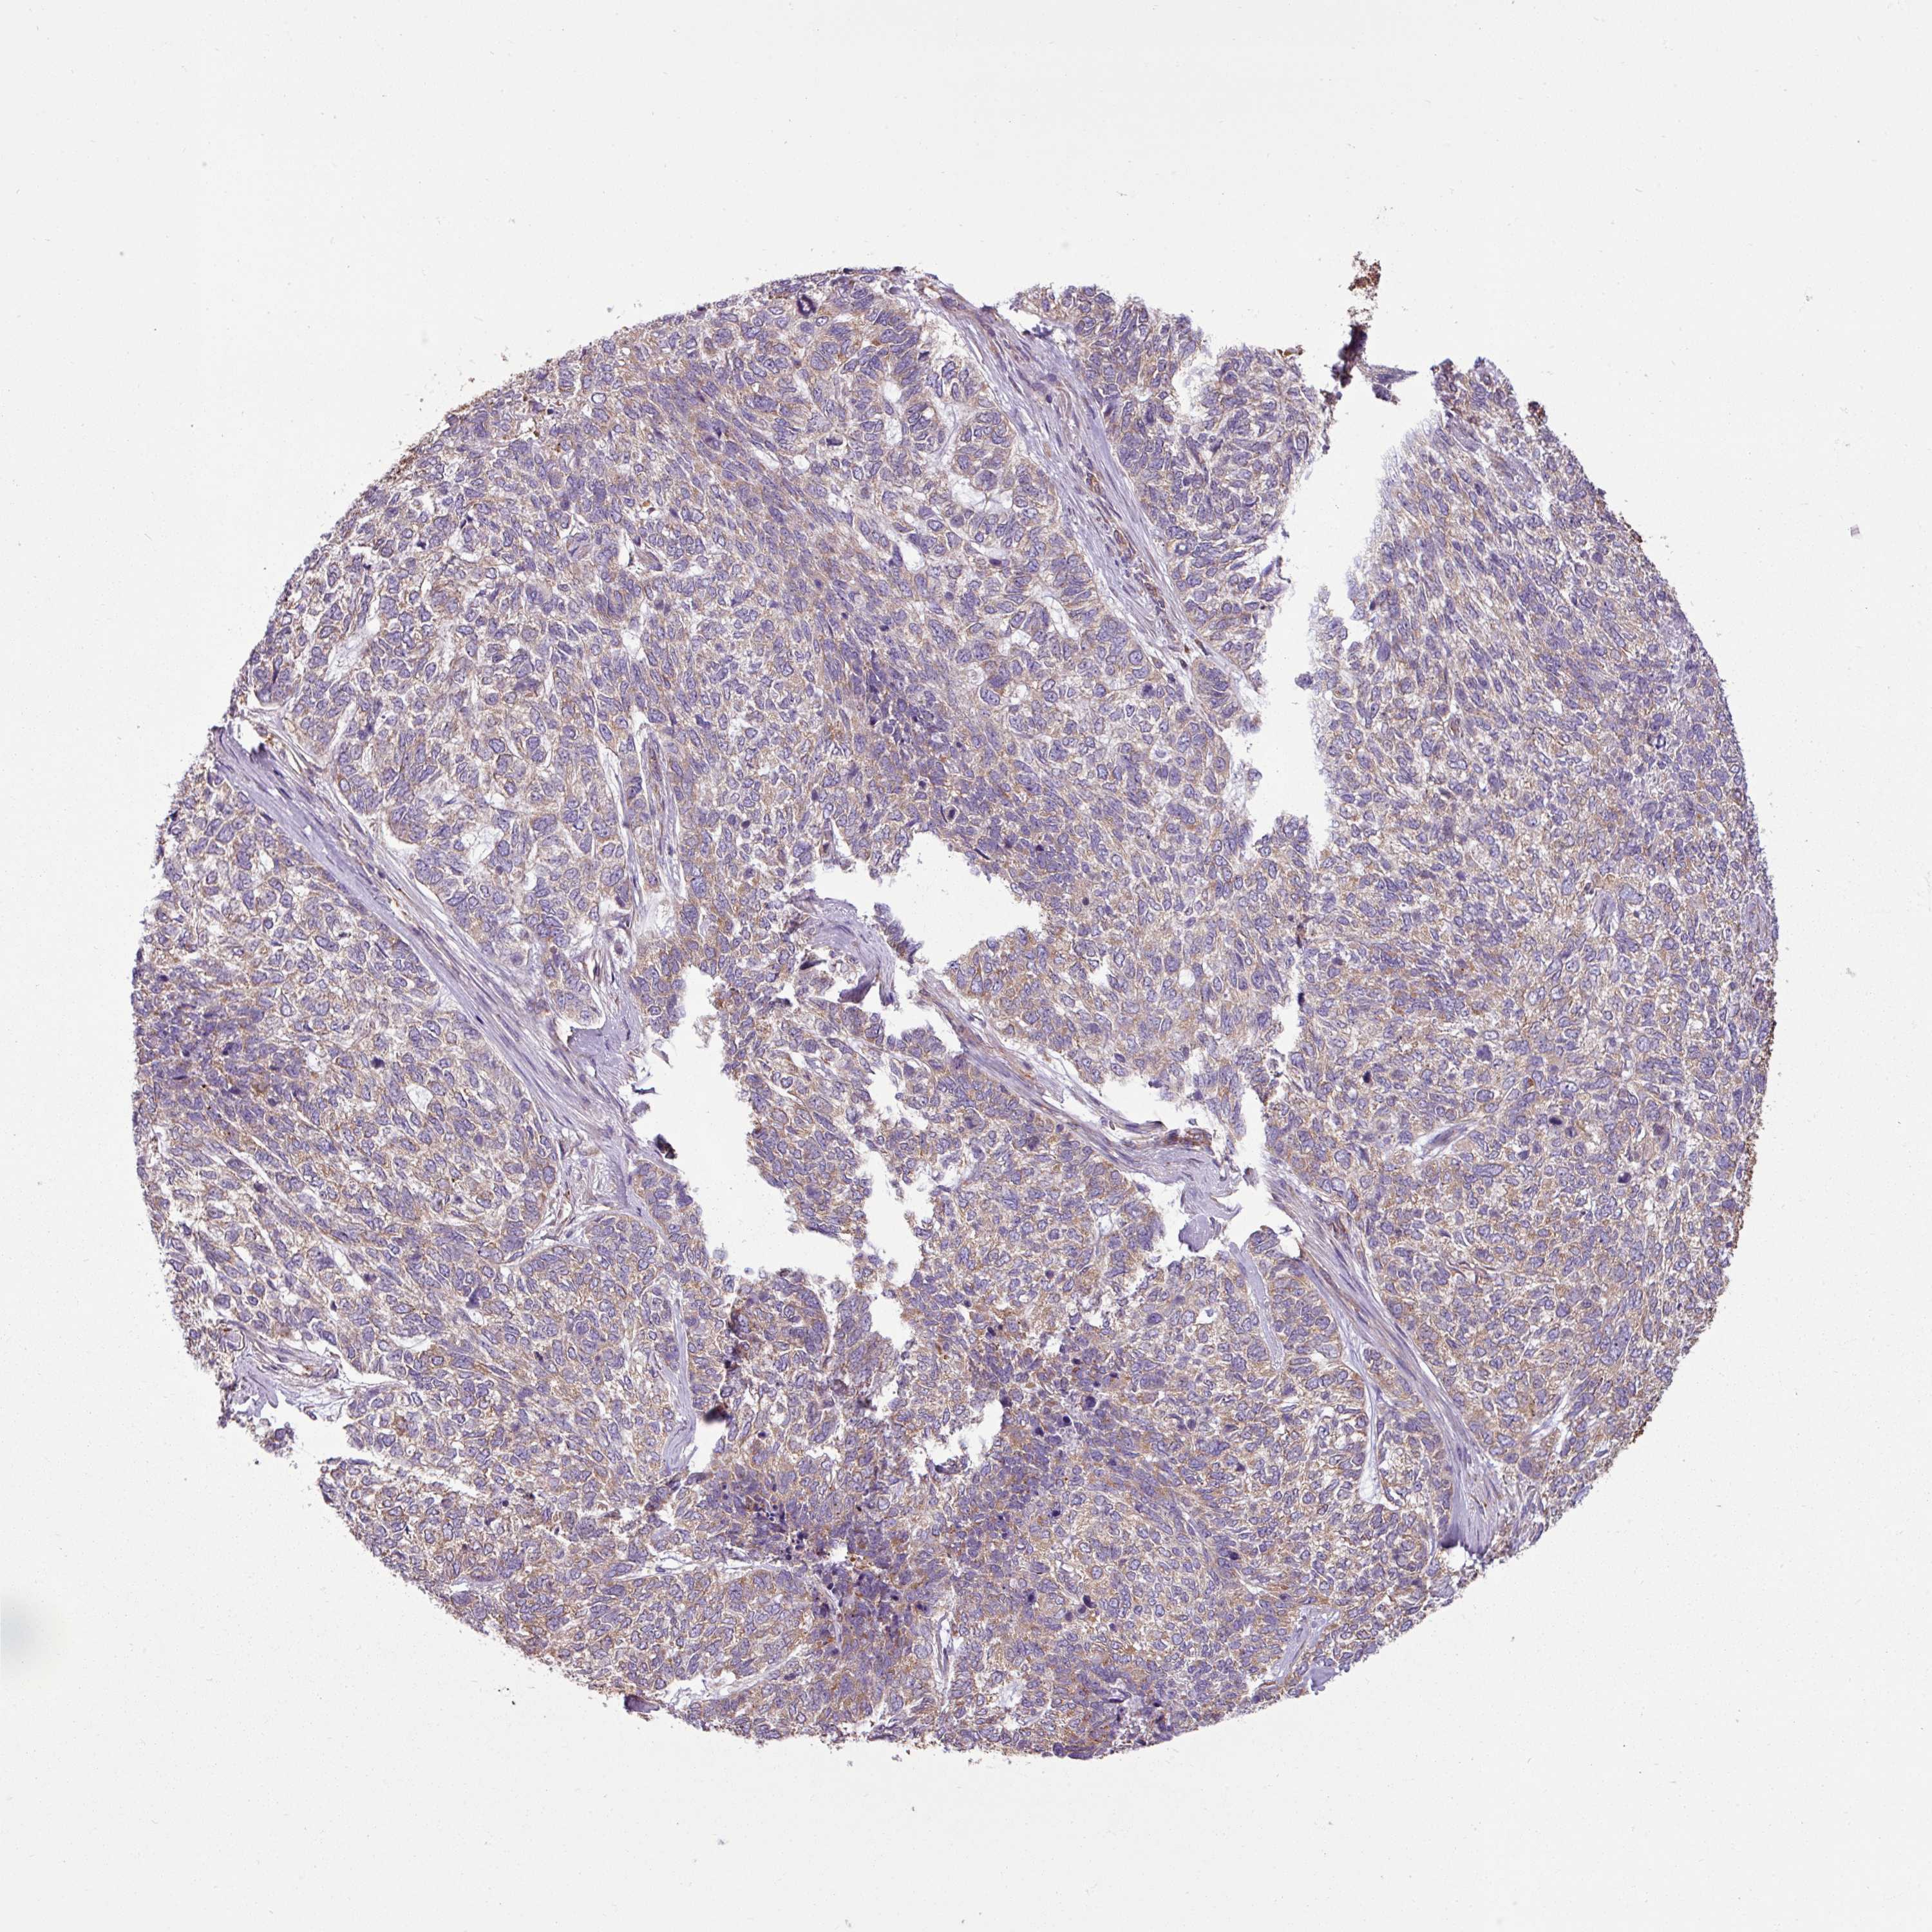

Basal cell and squamous cell cancer

SKIN CANCER - Protein expressioni

A mouse-over function shows sample information and annotation data. Click on an image to view it in a full screen mode. Samples can be filtered based on level of antibody staining by selecting one or several of the following categories: high, medium, low and not detected. The assay and annotation is described here.

Antibody stainingi

Antibody staining in the annotated cell types in the current human tissue is reported as not detected, low, medium, or high, based on conventional immunohistochemistry profiling in selected tissues. This score is based on the combination of the staining intensity and fraction of stained cells.

Each image is clickable and will lead to virtual microscopy that enables deeper exploration of all samples and also displays staining intensity scores, fraction scores and subcellular localization as well as patient and tissue information for each sample.

Antibody HPA049854

Antibody HPA056520

Staining

High

Medium

Low

Not detected

Intensity

Strong

Moderate

Weak

Negative

Quantity

>75%

75%-25%

<25%

None

Location

Nuclear

Cytoplasmic/membranous

Cytoplasmic/membranous,nuclear

Basal cell carcinoma

Squamous cell carcinoma, NOS

Squamous cell carcinoma, metastatic, NOS